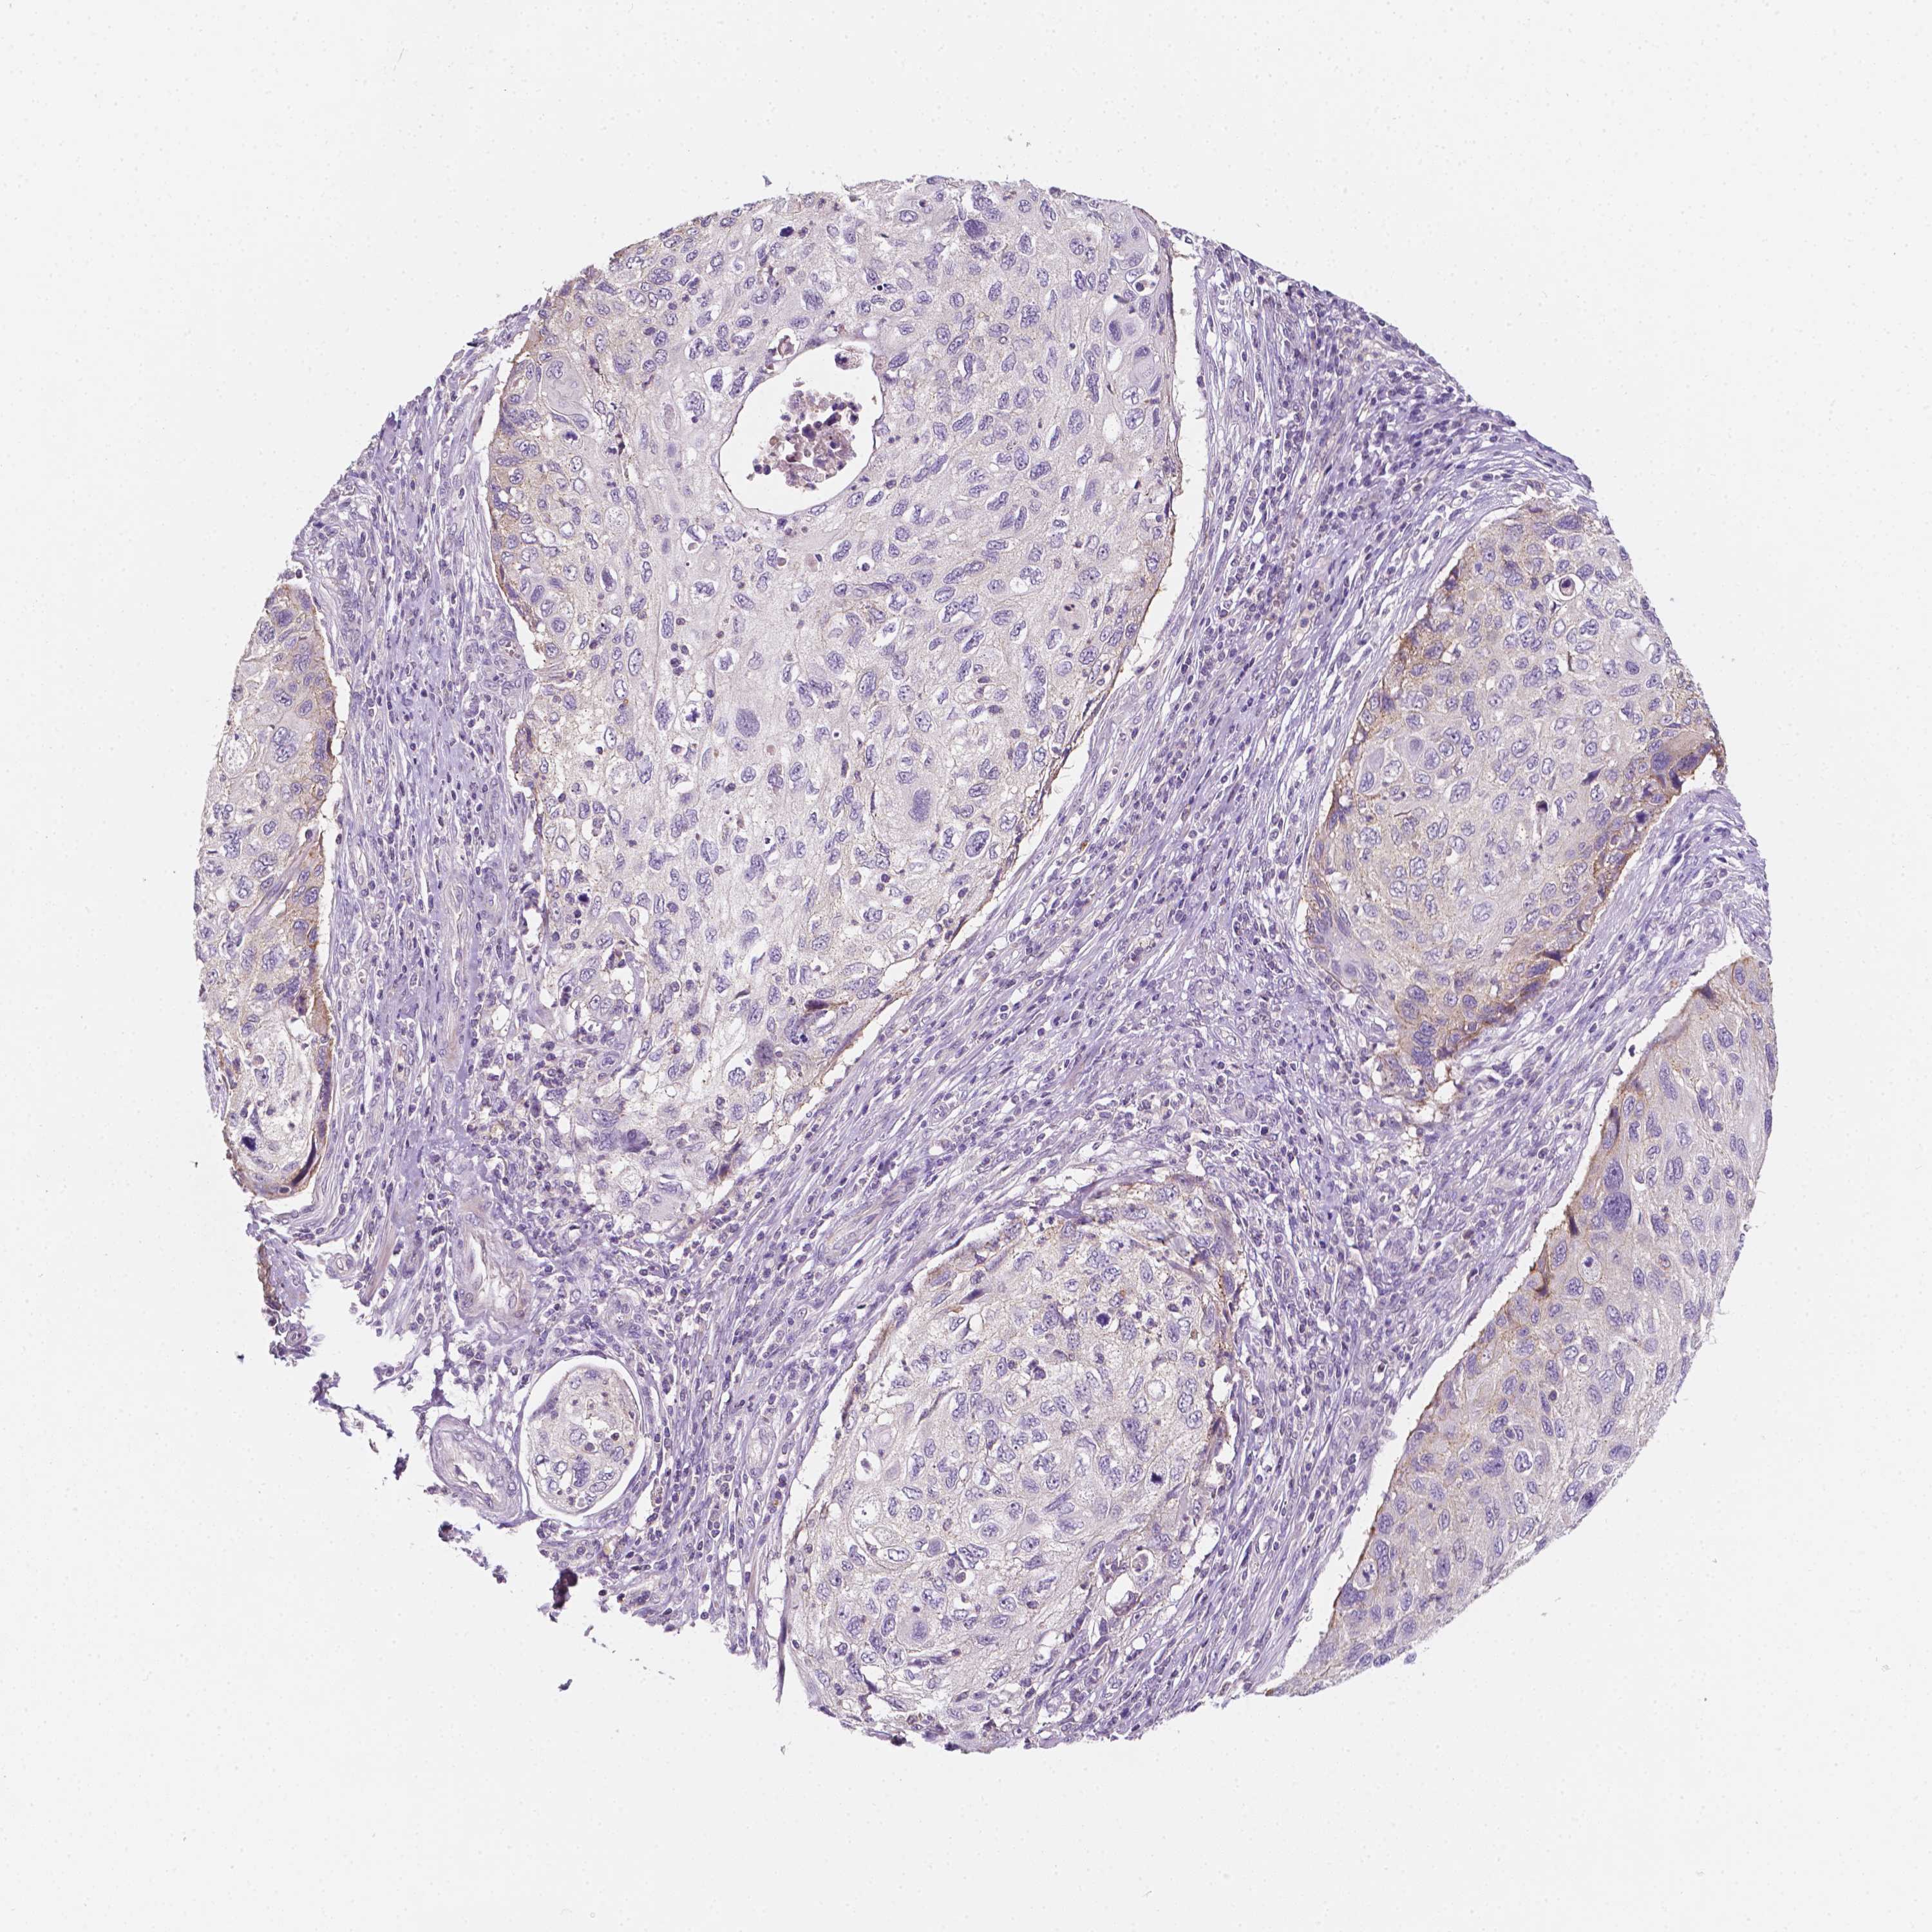

CERVICAL CANCER - Protein expressioni

A mouse-over function shows sample information and annotation data. Click on an image to view it in a full screen mode. Samples can be filtered based on level of antibody staining by selecting one or several of the following categories: high, medium, low and not detected. The assay and annotation is described here.

Note that samples used for immunohistochemistry by the Human Protein Atlas do not correspond to samples in the TCGA dataset.

Antibody stainingi

Antibody staining in the annotated cell types in the current human tissue is reported as not detected, low, medium, or high, based on conventional immunohistochemistry profiling in selected tissues. This score is based on the combination of the staining intensity and fraction of stained cells.

Each image is clickable and will lead to virtual microscopy that enables deeper exploration of all samples and also displays staining intensity scores, fraction scores and subcellular localization as well as patient and tissue information for each sample.

Staining

High

Medium

Low

Not detected

Intensity

Strong

Moderate

Weak

Negative

Quantity

>75%

75%-25%

<25%

None

Location

Nuclear

Cytoplasmic/membranous

Cytoplasmic/membranous,nuclear

Adenocarcinoma, NOS

Squamous cell carcinoma, NOS